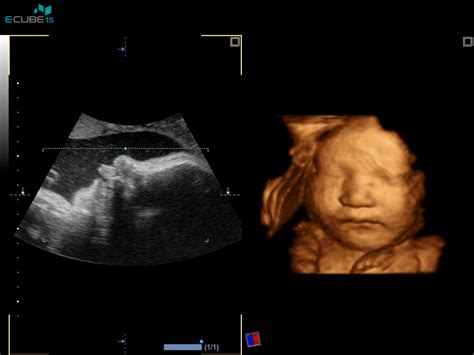

Pri medenični vstavi plod leži v maternici tako, da je proti izhodu iz porodni kanal usmerjen njegov spodnji del - ritka ali nogice. Najpogostejša je ritna vstava, kjer je ritka obrnjena navzdol, nogice pa so lahko pokrčene ob telesu ali iztegnjene navzgor. V redkih primerih gre lahko za nožno vstavo, kjer je ena ali obe nogici usmerjeni navzdol.

Zunanji obrat ploda

V mnogih porodnišnicah, še posebej v Ljubljani, se kot prva možnost ponudi zunanji obrat ploda. Ta postopek poteka okoli 37. tedna nosečnosti, ko zdravnik s pomočjo ultrazvoka oceni lego otroka, količino plodovnice, velikost materine medenice in prostornino. Če so pogoji ugodni, skušajo otroka z nežnimi gibi skozi trebušno steno obrniti v glavično lego. Ta postopek ni vedno uspešen (uspešnost je približno 50-odstotna) in ni povsem neboleč, vendar je varen. V nekaterih porodnišnicah, kot je Kranj, se obrat izvede po določenem protokolu, ki vključuje nekajdnevno hospitalizacijo in jemanje določenih zdravil za sproščanje mišic.